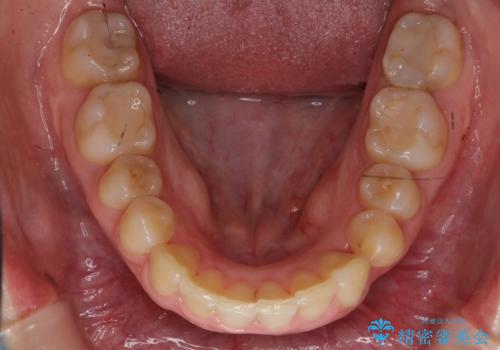

- 前歯の並びと下の歯のがたつきを主訴に来院。

左下にがたつきが集中していました。

歯を抜かずに、左上および左下の奥歯を後ろに送ることで隙間を確保しました。

左下の第一小臼歯が歯列からはみ出て、近心傾斜しており、抜歯の上ワイヤー矯正の選択肢もお話ししましたが、非抜歯で、インビザライン矯正を希望されました。左下の第一小臼歯は完全に並べることは難しいと初めから説明し、納得いただいた上で治療開始しました。

結果それなりに並んで問題ない状況にはなったと思います。

奥歯を後ろに送るために、矯正用ミニスクリューを使用しました。

また、下顎の前歯から奥歯にかけて歯を少し削るIPRを行なっています。